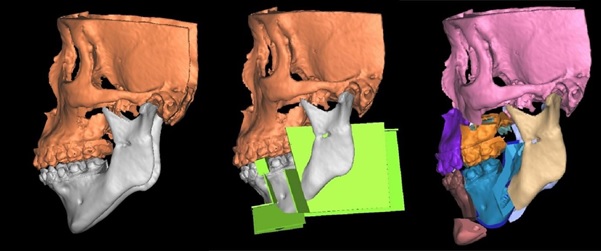

3D surgical planning of the SMA as part of the jaw advancement surgery for patients with severe obstructive sleep apnea.

The jaw surgery technique involves a multi-segment osteotomy (cutting and reshaping bones) of the lower jaw called segmental mandibular advancement (SMA). It is a combination of a procedure to upright the anterior jaw segment to create space and a procedure to advance the whole lower jaw.

The surgery is done to bring about significant enlargement of the skeletal airway at the base of the tongue, as well as an appealing aesthetic of the face and functional outcome in the bite.